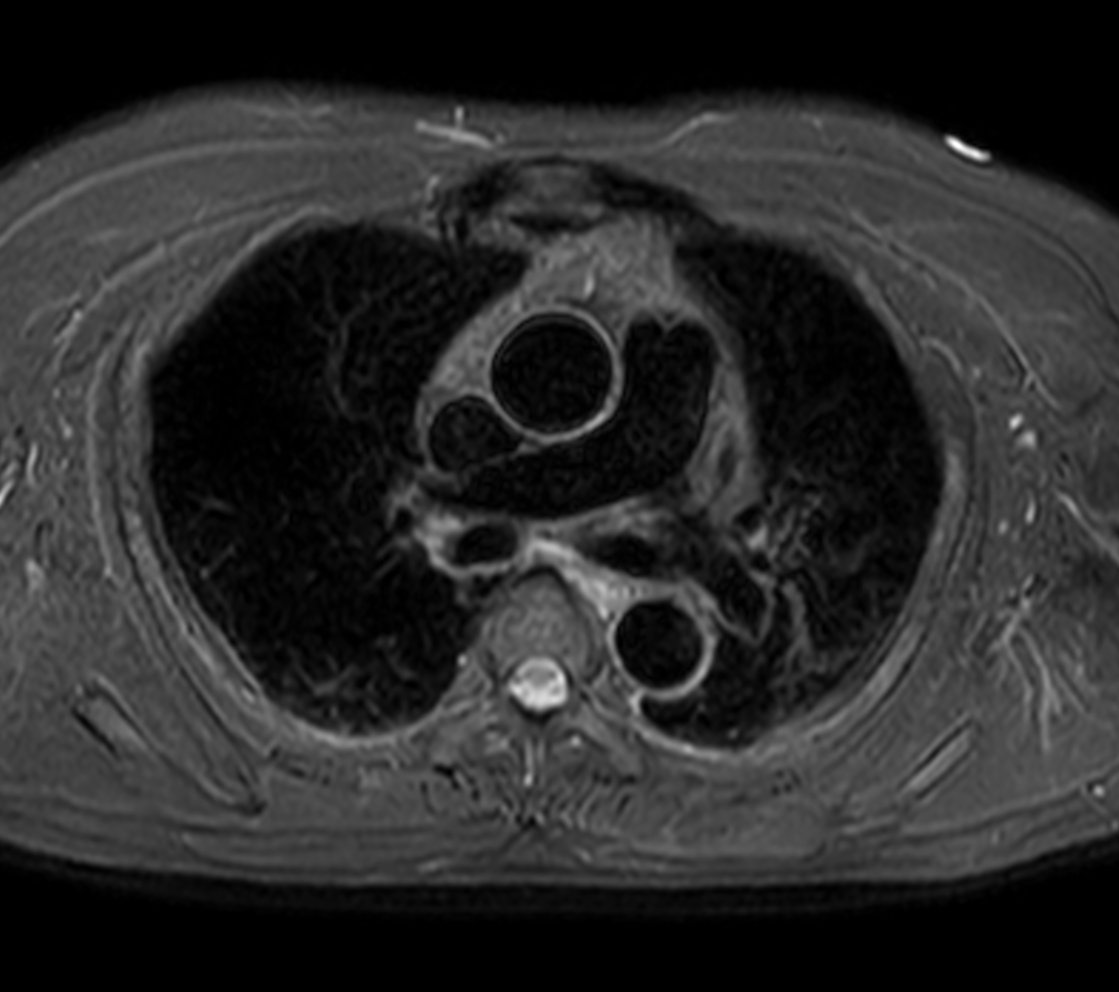

Axial MultiVane XD - T2w SPIR